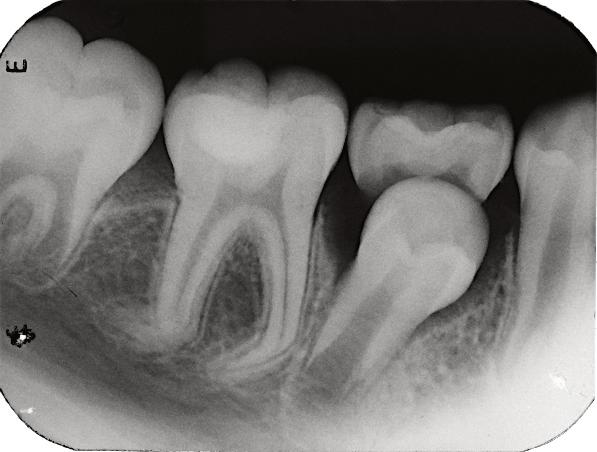

8.Biodentine®AnalternativeinVitalPulpTherapyinYoungPermanentTeeth.ClinicalCase,40monthFollow-Up. (Pgs.88-96)

Biodentine®UnaalternativaenlaTerapiaPulparVitalenDientesPermanentesJóvenes.CasoClínico.Seguimientode40Meses.

LuisDavidRamosFlores,DDS,